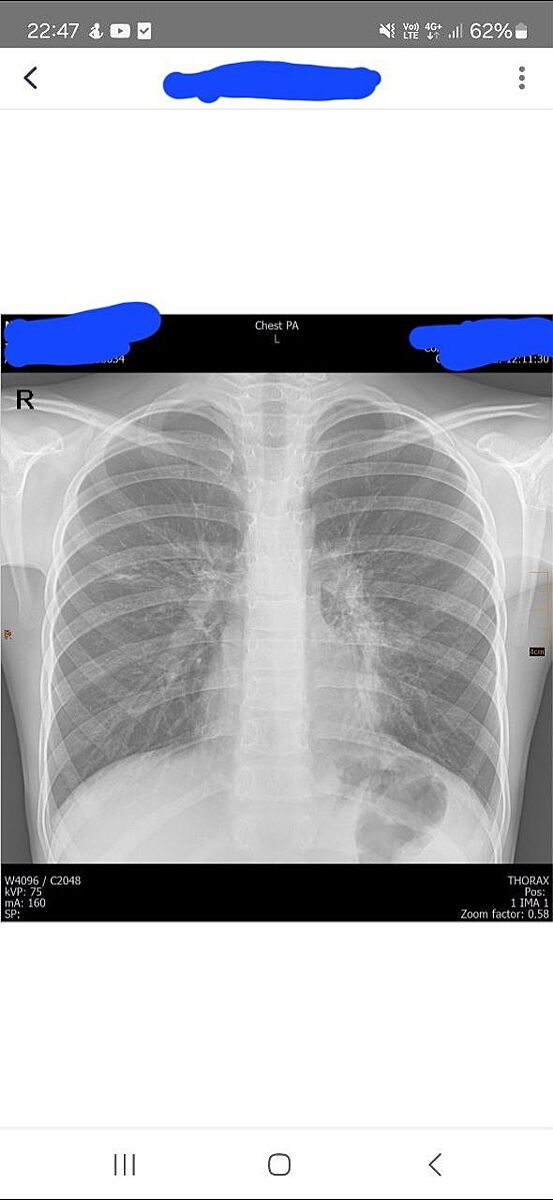

Рентген легень. Чи є пневмонія?

Висока температура у дитини, погано збивається. мокрий кашель. Лікар казала, що прослухати нічого підозрілого не може. Зробили сьогодні. Чи може хтось сказати, чи є на рентгені щось підозріле?

Немає запалення

Ні. Але на рентгені пневмонія виглядає як затемнення певних частин, такі темні плями. У вас легені чисті на знімку

Я вижу, что на рентгене легкие чистые.

на жаль, лікар сказав, що пневмонія. ми вже в лікарні. тут і хрипи чують((

Пневмонія це білі плями, а не темні

на жаль, там таки пневмонія

на жаль, це таки пневмонія